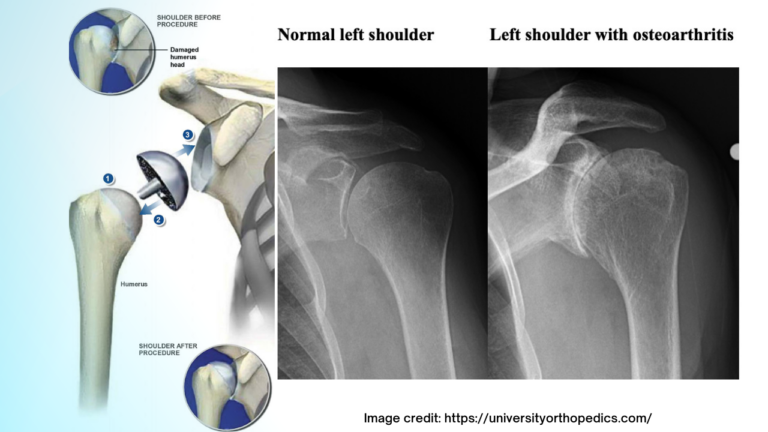

Patient Follow up: Shoulder Resurfacing This patient had a right shoulder replacement nearly a decade ago! What is a shoulder resurfacing procedure? A shoulder resurfacing procedure in orthopedics is a surgical technique designed to treat certain shoulder conditions, primarily arthritis, by preserving as much healthy bone and tissue as possible while addressing the damaged surfaces… [Read More]